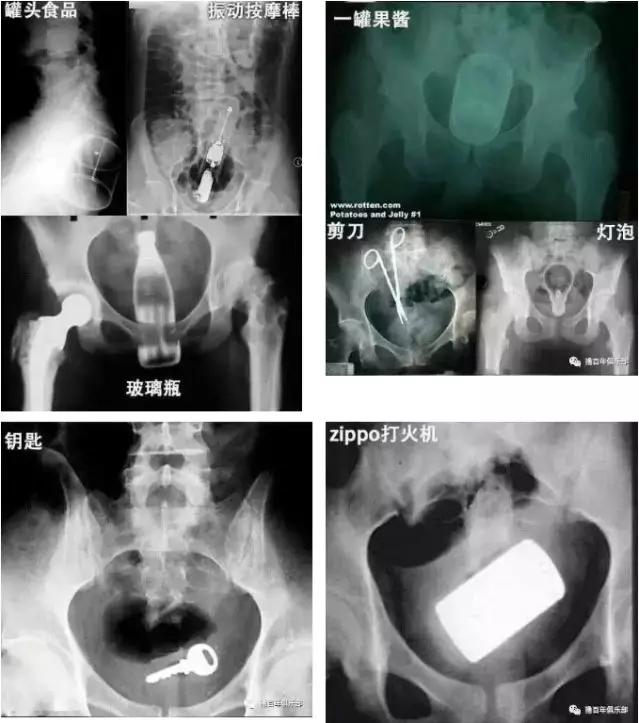

只有你想不到,没有大家做不到的!玻璃瓶、剪刀、灯泡、钥匙.....

直肠不是哆啦A梦的口袋大家千万别乱来啊!如果异物不慎进入直肠后,一定要及时就医,以免延误病情,造成严重后果!